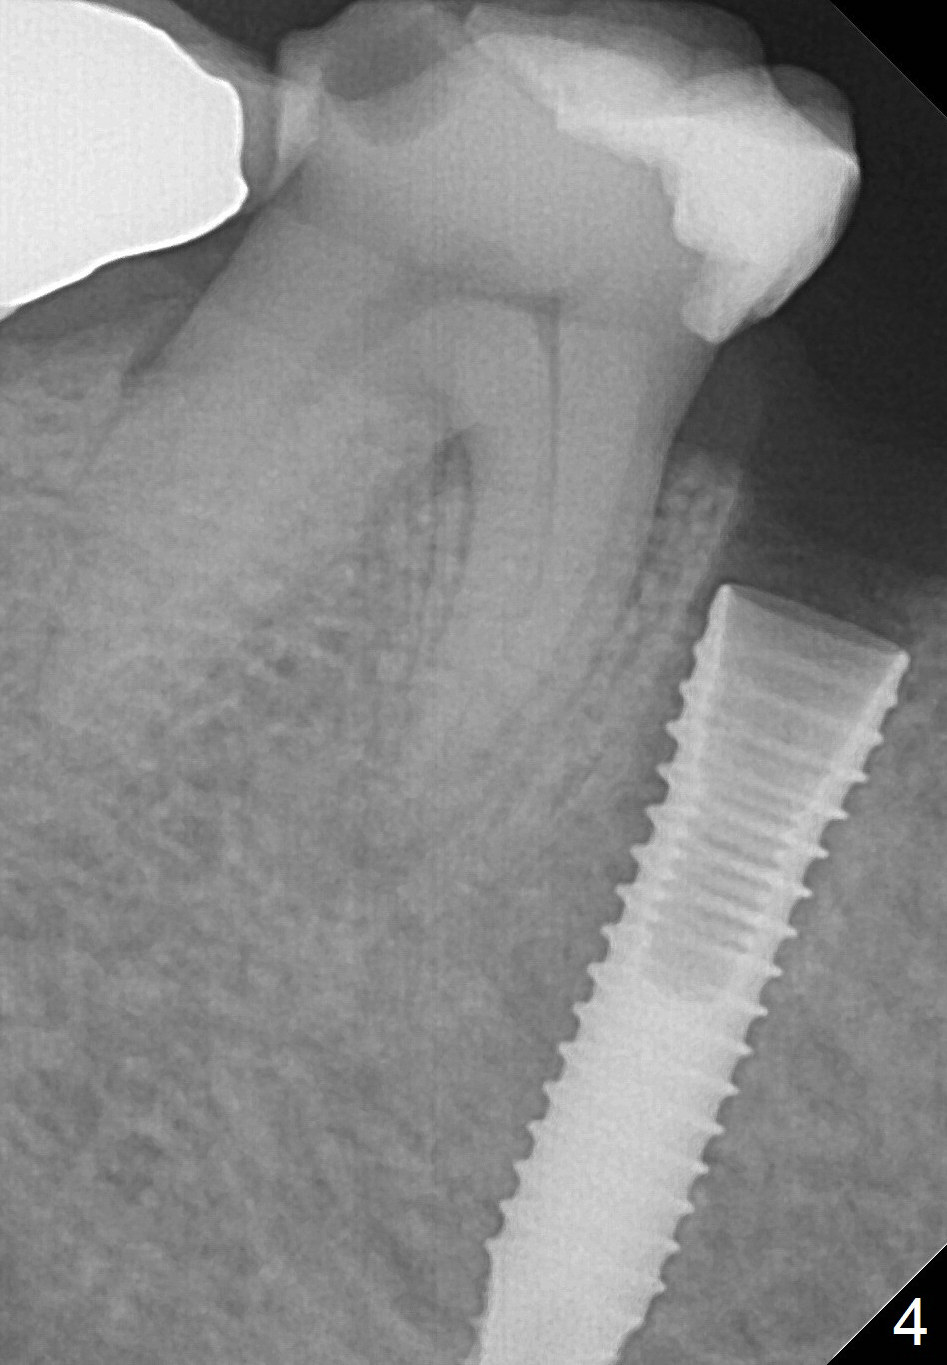

A 67-year-old woman fractures the tooth #29 three months post RCT. There is persistent periapical radio-lucency (Fig.1 yellow dashed line), which is close to the Mental Loop (red dashed line). Since the root of the affected tooth deviates distal, osteotomy will be established mesial (Fig.2). In fact it is not so easily accomplished; the osteotomy is initiated as mesial as possible (Fig.3 (yellow dashed line: original socket)). When a 3.8x16 mm implant is being placed, it is distal (Fig.4). The MO composite of the tooth #30 has to be trimmed for fabrication of an immediate provisional (Fig.5 <).

To place the implant mesially, the initial osteotomy should be established higher in the mesial slope of the socket (Fig.3 red line). Once the drill penetrates the lamina dura (Fig.5 short black line), change the trajectory (Fig.5 red line). A potential drawback may be loss of primary stability when osteotomy increases.

To reduce the chance to injury the buccally located loop, the osteotomy should be as lingual as possible. Initial depth is 19 mm (gingival level, Fig.3). In fact all of the three intraop PAs (Fig.3-5) do not show the Mental Loop until panoramic X-ray is taken immediately postop (Fig.6). There is no postop paresthesia. There appears no gap around the implant 3.5 months postop (Fig.7 >).